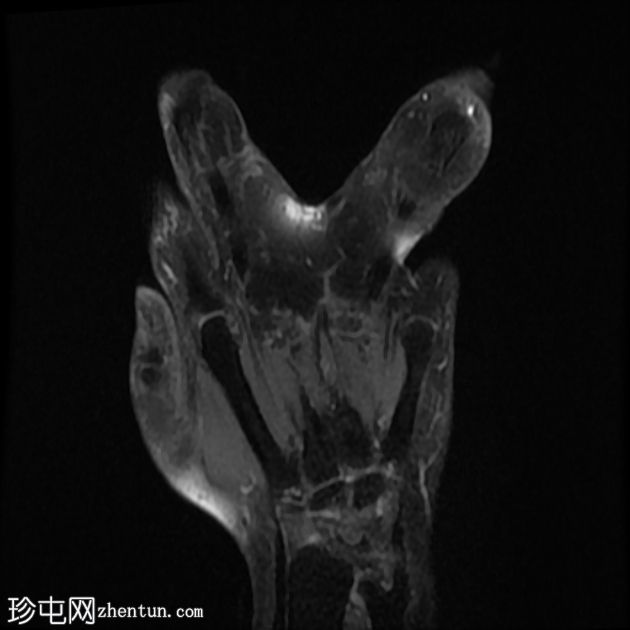

无名指和中指明显增大。患者掌骨和指骨骨质增生肥大,并伴有周围皮下脂肪过度增生。

支配患指的正中神经掌侧支纤维脂肪瘤性错构瘤。它们在矢状面序列上呈现意大利面条状,在轴位图像上呈现绳索状。

该病通常与神经纤维脂肪瘤性错构瘤有关。受影响的肢体通常遵循上肢正中神经的分布,就像本例一样。